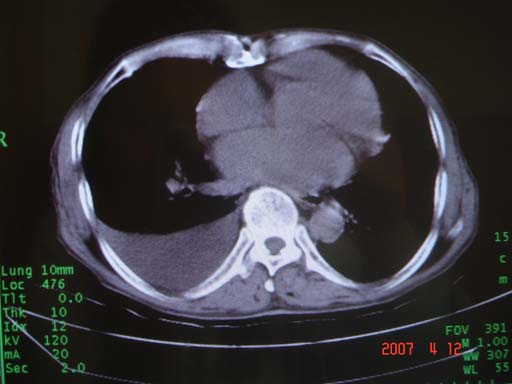

帮我 看看。男77岁咳嗽咯血2月发热2周!病人一般情况可 口痰为鲜红,有点象洗肉水(我看见他吐的痰了)

考虑右肺新生物伴右中上肺阻塞性肺炎及含气不良,右侧胸腔积液。建议痰与纤支镜检查

考虑右侧中央型肺癌伴中上肺阻塞性肺炎、不张,胸腔积液。,建议支纤镜检查。

病灶局限在右肺中上叶,呈大片状实变影,内见空气支气管征,支气管分支较柔软,纵隔内未见肿大淋巴结.支持:感染性病变_1 大叶性肺炎.2 干酪性肺炎.

优先考虑右上肺干酪性肺炎并同侧中叶播散、胸腔积液。分析:右膈肌未见升高、纵隔未见明显右移,胸部各组淋巴结未见可疑肿大,中叶可见支气管铸形,肺野、肺门未见可确定肿块。

年龄偏大,应考虑右肺中央型肺癌并阻塞性肺炎 阻塞性肺不张,胸腔积液

考虑右侧中心型肺癌伴中叶肺不张,右侧 胸腔积液

右肺上叶中心型肺癌并上叶阻塞性肺炎,中叶炎症,右侧胸腔积液

右肺上叶后段支气管中断,首先考虑中央型肺癌并右肺不张及纵隔淋巴结转移,右侧胸腔积液。

有点象洗肉水的痰,其来源应当是实变引起的血细胞渗出导致,可见支气管气象,实变区有虫蚀状空洞,有明显胸腔积液,未见明显肺门区肿块影,考虑继发型肺结核,干酪性肺炎